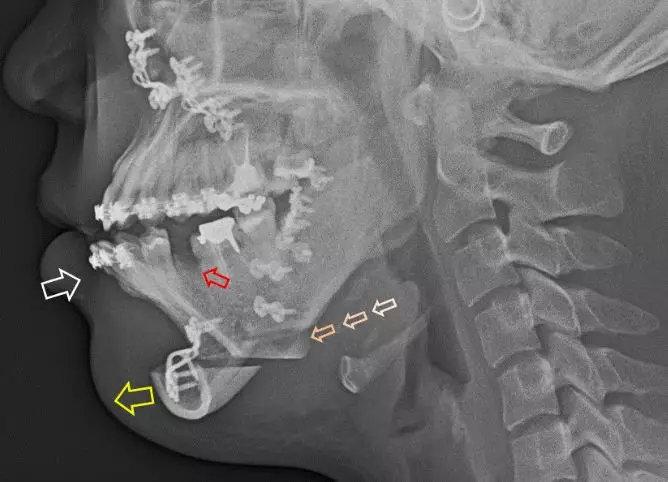

骨性龅牙除了牙齿矫正外,还要做正颌手术,就是根据实际问题将突出的上颌骨或下颌骨去掉部分内推,让嘴型变得正常,有的还可能要配合进行隆下巴或下颏前移手术。

▼手术示意

▼正颌手术后X光照片